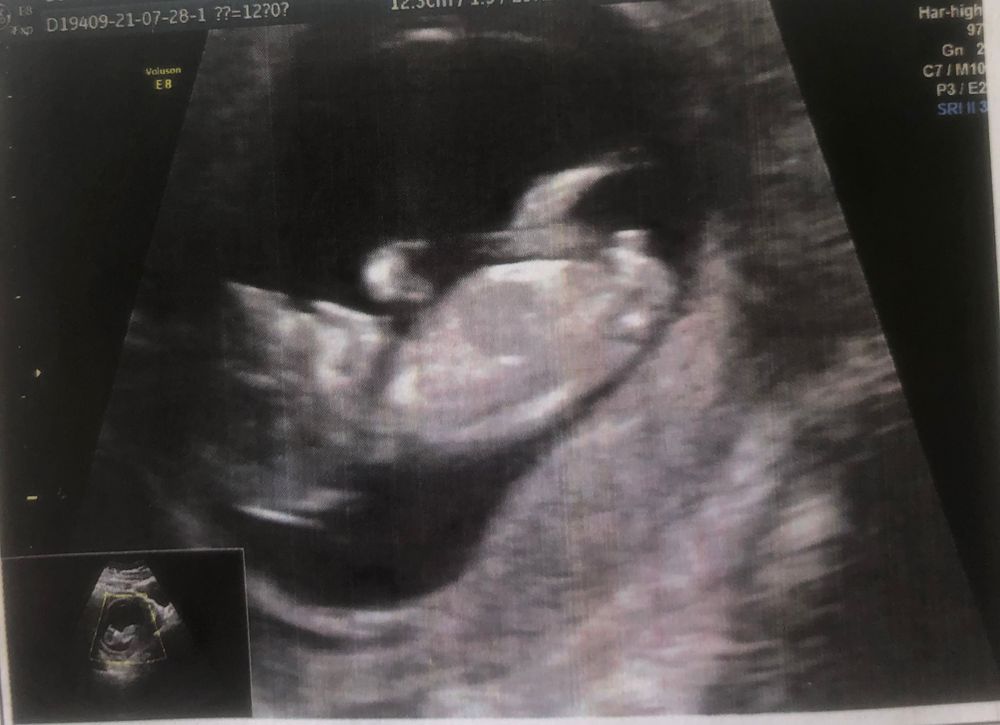

Мой малыш 12 неделька ❤️

Мальчик)

Похоже на мальчика)

Сыночек похоже)))

На мальчика похож

Мальчик